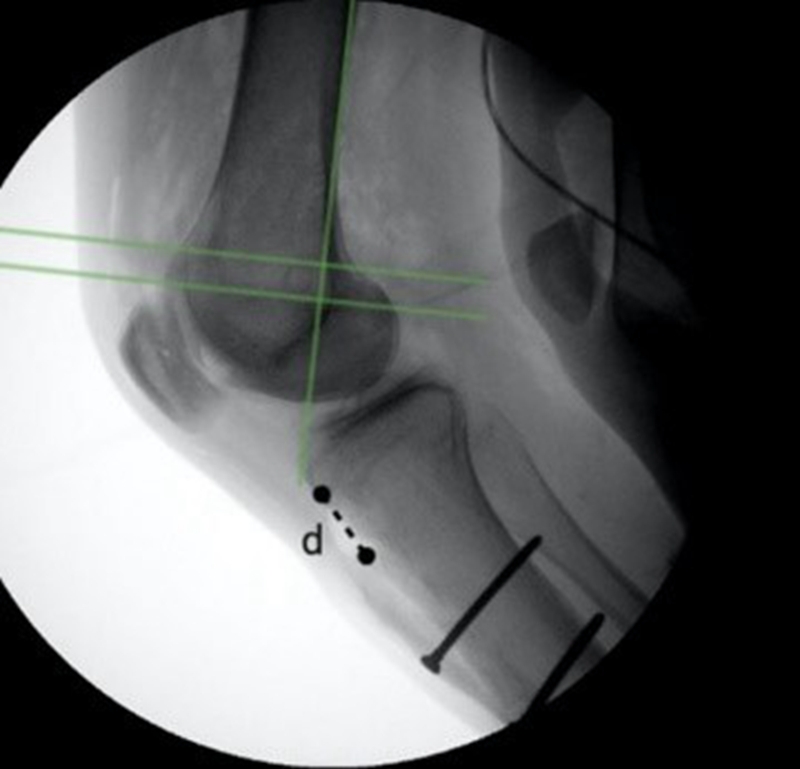

Anouk等人分析ACLR翻修联合胫骨去屈曲截骨术(TDO)的9名患者数据,指出在术后7-15年与术后2-8年随访结果相比,患者的临床评分保持或改善,没有再撕裂或再次手术的情况。证实TDO可以防止ACL移植物再撕裂,在进行ACLR时,无论是翻修还是初次手术,都应考虑矫正过度的胫骨后倾[6]。

图4